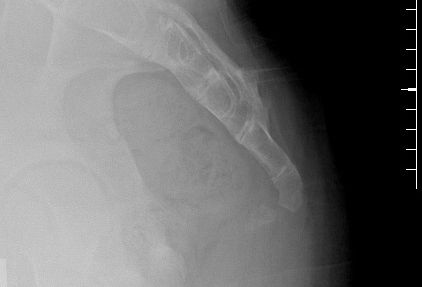

Radiografia sacrococcígea lateral de uma paciente com coccigodinia crônica pós-traumática, mostrando a sinostose sacrococcígea (fusão, variante normal) e a subluxação anterior de Co1-Co2

Do acervo pessoal do Dr. R. Schrot